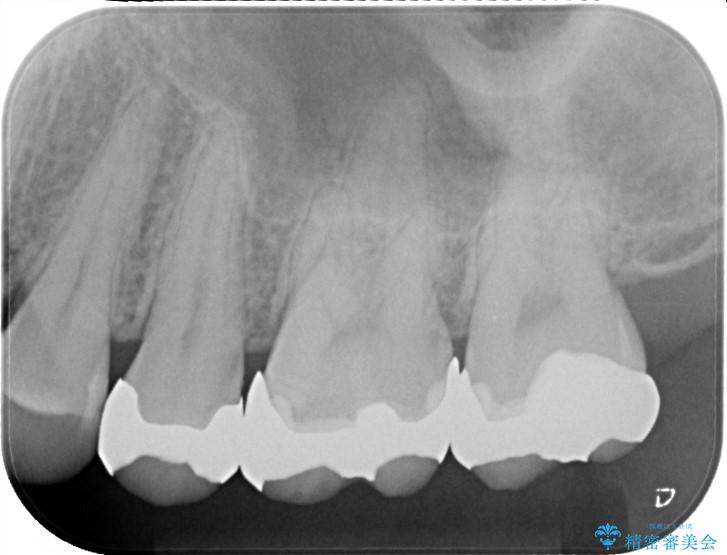

銀歯が綺麗な白い歯になりました。

適合がとてもよいので、フロスの引っかかりも解消されました。

一番奥の歯は銀歯に覆われている範囲が多いため、強度などを踏まえ被せ物にしました。

その他2本は詰め物です。